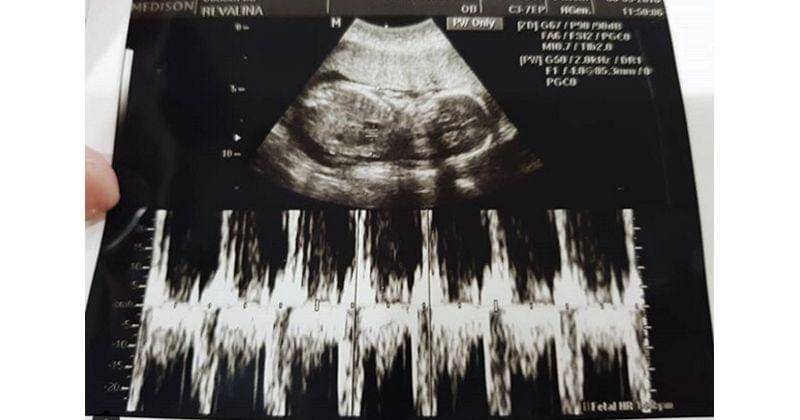

Melalui akun Instagram miliknya, @vatemat, Revalina mengumumkan bahwa ia kini tengah hamil anak kedua. Kini usia kehamilan Revalina sudah memasuki 22 minggu.

Ya, beberapa waktu lalu ia mengunggah foto USG sang buah hati. Revalina juga menceritakan kehamilannya kali berbarengan dengan sang adik.

"Assalamualaikum baby.. sehat2 ya nak, kita udh setengah jalan nih.. kmrn pas kontrol rame bgt, ada bapak, akang rihga, genma, didi n uncle agi. Kebetulan hamilnya barengan sama adikku, jd kmrn bener2 dijadwalin kontrol babynya barengan," tulis Revalina.